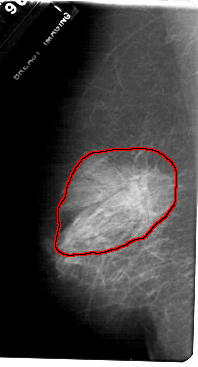

FILE: A_1720_1.LEFT_CC.OVERLAY

TOTAL_ABNORMALITIES 1

ABNORMALITY 1

LESION_TYPE MASS SHAPE ARCHITECTURAL_DISTORTION MARGINS SPICULATED

ASSESSMENT 2

SUBTLETY 5

PATHOLOGY BENIGN_WITHOUT_CALLBACK

TOTAL_OUTLINES 1

BOUNDARY